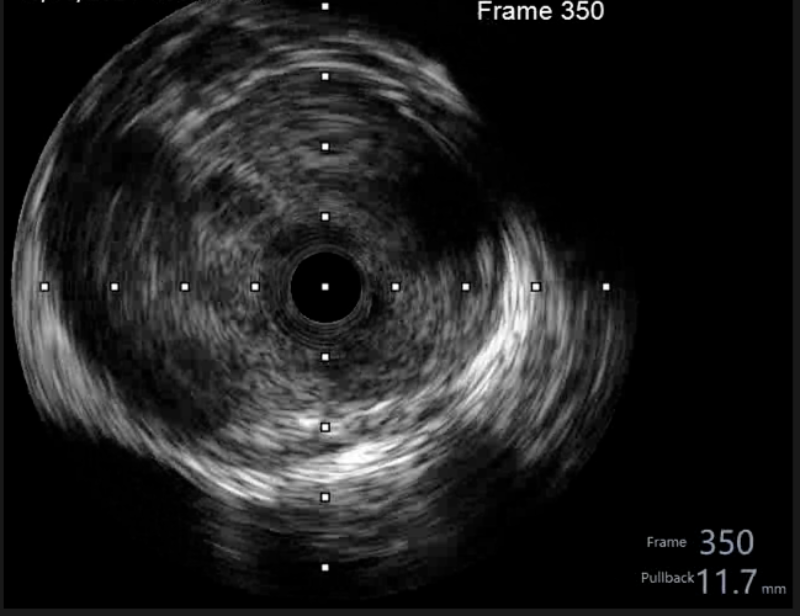

在惠州市中心人民医院派驻中文博彩平台分院专家、中文博彩平台分院心血管内科谢桂庭主任和谢志恒科副主任的带领下,成功开展了中文博彩平台分院第一例冠状动脉血管内超声(IVUS)检查。术中行冠状动脉血管内超声(IVUS)检查:回旋支中段瘤样扩张,少量血栓影,最大管腔直径约6mm,未见夹层、血肿(图4、5)。患者病变为冠脉瘤样扩张并血栓形成,予抗栓等治疗后患者好转出院。

(图4)

(图5)